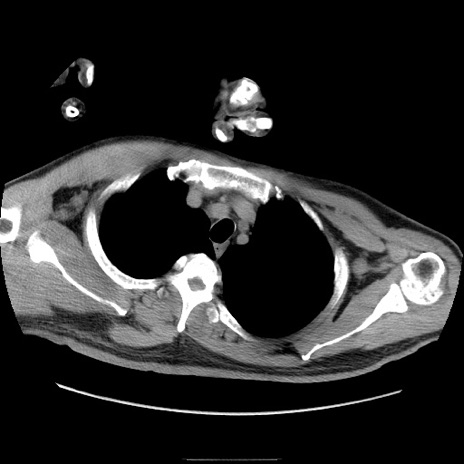

症例